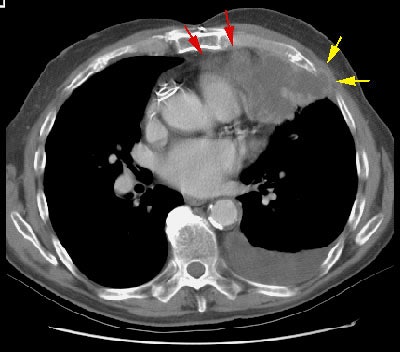

Example 2: In this patient with non-small cell lung cancer there is extension of the tumor between the ribs into the chest wall (yellow arrows). Disruption of the fat planes within the mediastinum (red arrows) is highly suggestive of mediastinal invasion as well. The lesion also abuts the main pulmonary artery.

Example 2: This patient with non-small cell lung cancer demonstrates many findings which are suspicious for mediastinal invasion. There is greater than 3 cm of contact between the mass and the mediastinum, loss of the mediastinal fat plane between the mass and the left pulmonary artery, deformity of the left pulmonary artery, and pericardial thickening (yellow arrows). The patient also demonstrates contralateral mediastinal adenopathy (N3 nodes -- white arrow), subcarinal adenopathy (SC), and bilateral pleural effusions.

NOTE:  Click image to enlarge